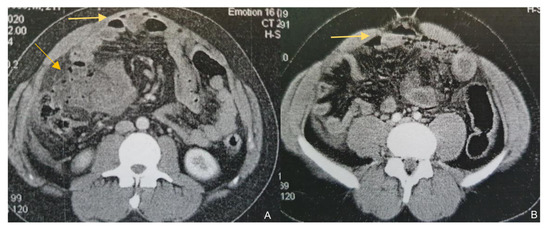

A 23-year-old male was referred to the surgical department from another hospital for further investigation and management of a high-output enterocutaneous fistula and possible short bowel syndrome. The patient’s medical history included several operations in the abdominal cavity due to recurrent incidents of intestinal perforations. His surgical problems had begun two years earlier, when he was admitted to the emergency department with acute epigastric pain, migrating within the next few hours to the right iliac fossa. Laboratory tests revealed leukocytosis (white blood cells (WBC) count 15.32 k/μL, neutrophils 87%) and increased C-Reactive Protein (CRP) at 1.9 mg/dL (normal range: <0.5 mg/dL). An abdominal Computed Tomography scan (CT scan) revealed free intra-abdominal air and pneumatosis of the descending and sigmoid colon (Figure 1). Thus, an exploratory laparotomy was performed, revealing generalized fecal peritonitis and a rupture on the antimesenteric wall of the sigmoid colon and confirming the diagnosis of gastrointestinal (GI) tract perforation. The hole was primarily sutured and the patient was discharged from the hospital on the 9th postoperative day, experiencing an uncomplicated postoperative period.

Figure 1.

Contrast-enhanced CT findings. Axial images of contrast-enhanced CT on presentation (A) and a subsequent episode of perforation (B). In both cases, a note is made of marked fat stranding, free intraperitoneal gas bubbles, and small bowel wall thickening, suggestive of small bowel perforation.